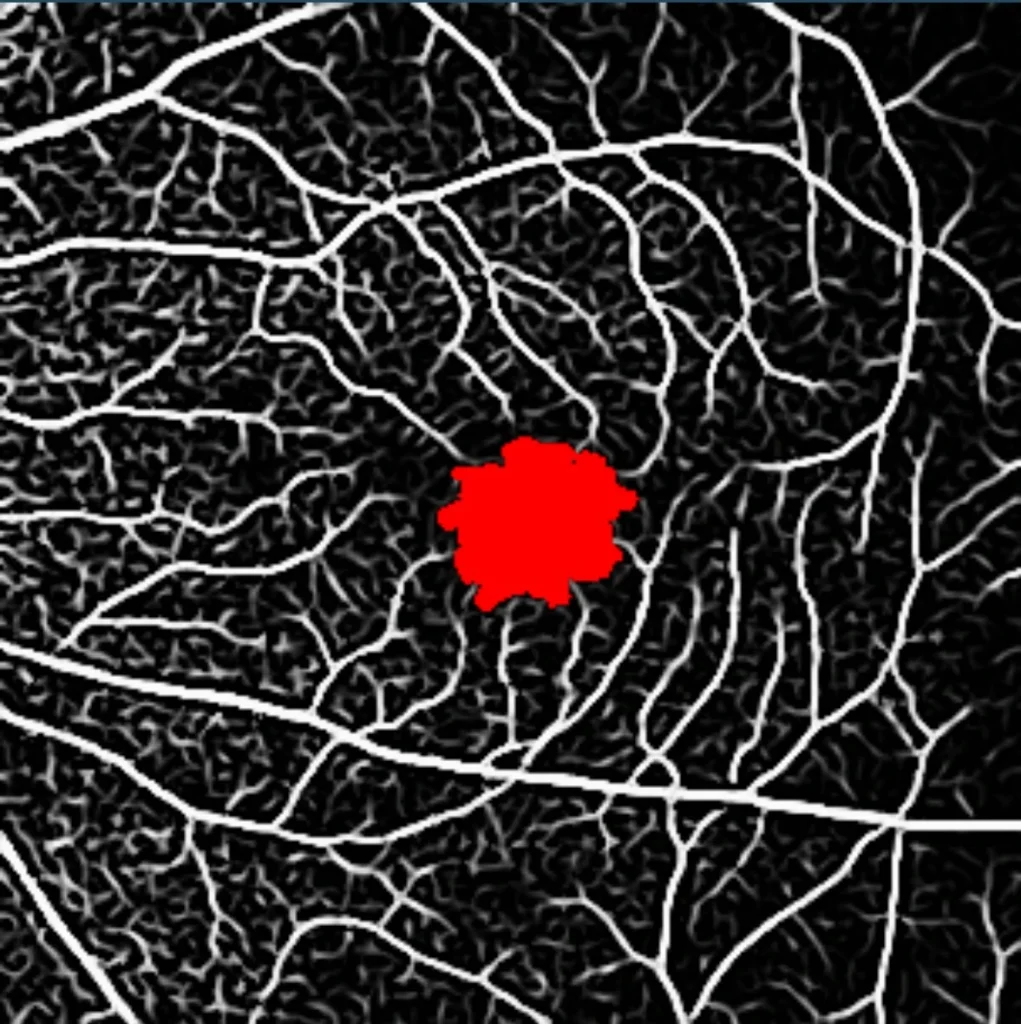

- Angiography:

- OCT – Angiography (OCT-A)

- Fluorescein Angiography (FA)

- Indocyanine Green (ICG) Angiography